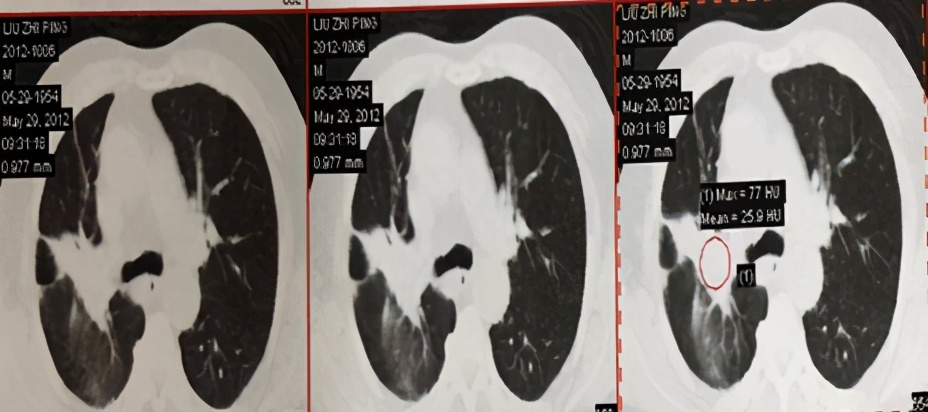

治疗后5年复查,患者偶有咳血,局部病灶纤维化改变